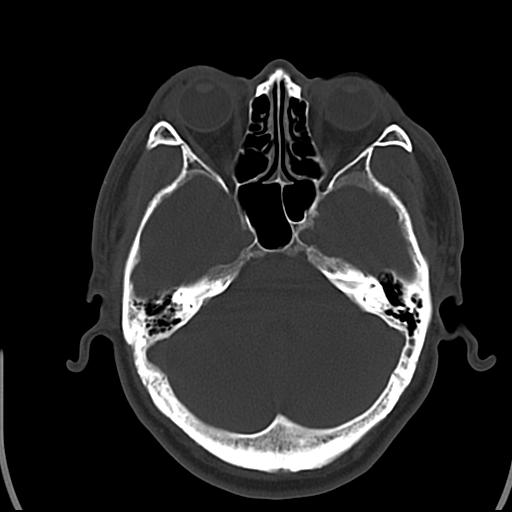

头皮下高密度结节影???临床上在老年男性比较常见。大家看看是什么?成因是? 本例患者,男性,51岁。外伤来诊。无染发史及发根植入史。

皮下钙化点

考虑钙化。

这种东西有时要结合触诊和望诊。